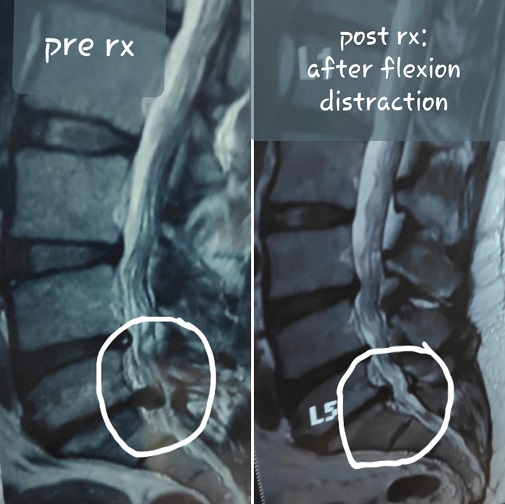

Flexion Distraction

3: Flexion Distraction

Decompression & Flexion Distraction

4: Decompression & Flexion Distraction